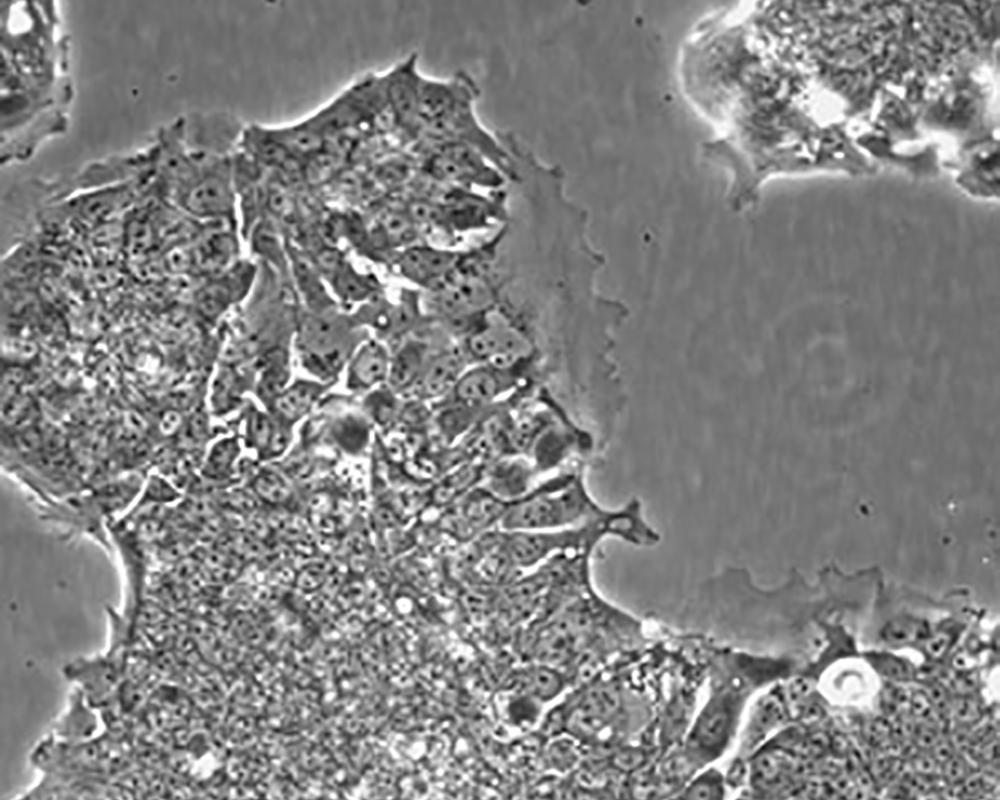

形態特征 epithelial

細胞描述 T84細胞株是從一位72歲男性結腸癌患者的肺轉移灶建立的可移植人類癌細胞株。 腫瘤組織皮下接種于BALB/c裸鼠,并連續進行移植。 [26072] 在裸鼠身上的移植過程中,細胞株始終保持結腸癌的原始組織性狀。 [26072] 在無胸腺小鼠中傳代23代后建立了T84細胞株。 這些細胞單層生長到飽和并在接觸細胞間展現出緊密連接和橋粒。 [1155] 有很多關于多肽類激素和神經遞質并維持定向電解質傳輸的受體。 [1155] 這株細胞展現了接觸細胞中的緊密連接和橋粒。 [1155] 角蛋白免疫過氧化物酶染色陽性。